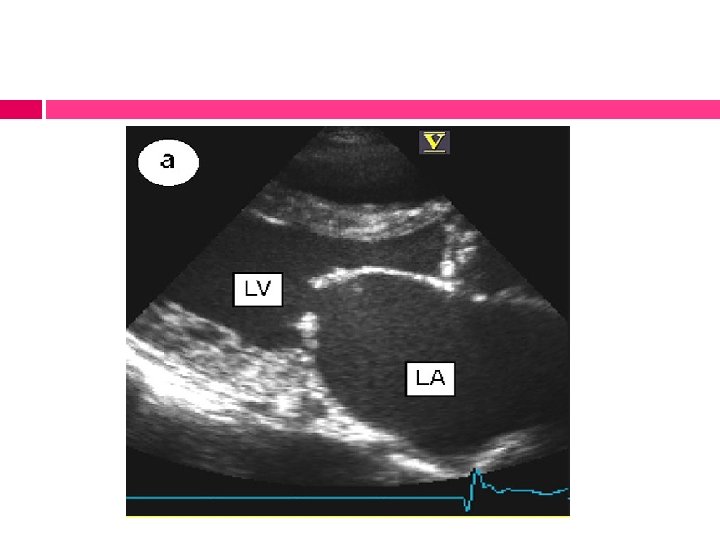

MITRAL INSUFFICIENCY Backflow of blood from the LV to the LA during systole

MITRAL INSUFFICIENCY Pathophysiology: v Loss of valvular substance & shortening & thickening of the chordae tendineae v Because of the high volume load & inflammatory process, the left ventricle becomes enlarged v The left atrium dilates as blood regurgitates into this chamber v Increased left atrial pressure results in pulmonary congestion & symptoms of left-sided heart failure

MITRAL INSUFFICIENCY Imaging studies: v ECG: prominent bifid P waves, signs of left ventricular hypertrophy & associated right ventricular hypertrophy if pulmonary hypertension is present v X-rays: prominence of the left atrium & ventricle; congestion of perihilar vessels, a sign of pulmonary venous hypertension v 2 D ECHO: enlargement of the left atrium & ventricle & Doppler studies demonstrate the severity of the mitral regurgitation